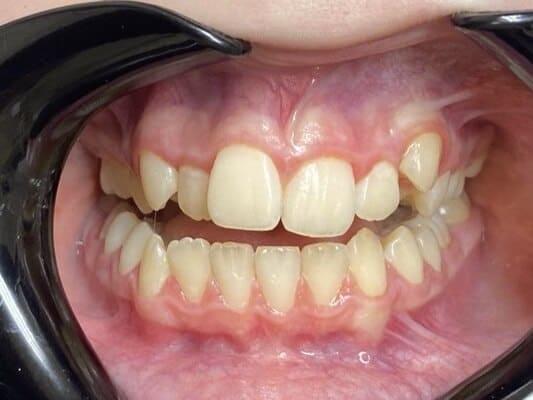

Пацієнт 2 років, уражено десять зубів, шість із яких потребують покриття коронками. В зв’язку зі значним об’ємом та складністю лікування прийнято рішення про лікування в умовах анестезіологічного забезпечення. Раніше була спроба пролікувати ці зуби застарілими методами, які не тільки не є ефективними відносно лікування, а ще і додають дитині комплексів через характерне фарбування зубів. Через високи естетичні вимоги дитини і батьків було прийнято рішення покривати естетичними цирконієвими коронками, як передні так і бічні зуби. Через 2,5 години дитина без інфекції в порожнині рота, з відновленим здоров’ям та естетикою посмішки може кусати, жувати, посміхатись без болю та дискомфорту. Останнє фото через 2 роки після лікування, оскільки естетичні коронки в дитячій стоматології - це надійність, естетика та функція.